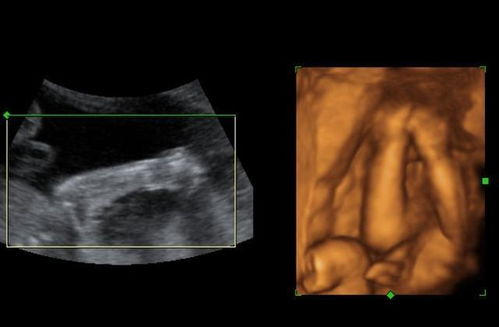

随着孕期进入22周,准妈妈们通常会进行系统彩超检查,也称为四维彩超检查。这项检查对于监测胎儿发育状况、排查潜在问题具有重要意义。本文将详细介绍22周系统彩超检查的内容。

系统彩超对胎儿的解剖结构进行全面检查,包括胎头、颜面部、颈部、胸部、心脏、膈肌、腹部、脊柱和四肢等。这一环节旨在发现胎儿是否存在任何发育异常或畸形。